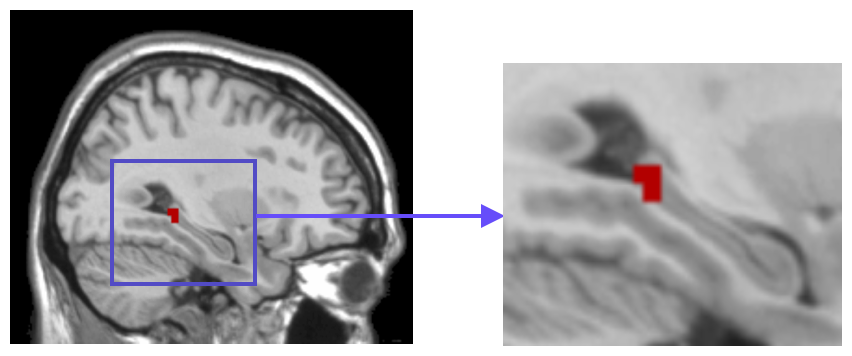

Usually, the first step of voxel-based neuroimage analysis requires preprocessing the T1-weighted image, such as segmentation and registration of grey matter (GM), white matter (WM) and cerebral spinal fluid (CSF). However, some systematic biases due to scanner difference and different population etc., can be introduced in this pipeline [2]. Part of them can be helpful to the discrimination of subjects from normal controls (NC), but may not be directly related to the disease. For example in structural Magnetic Resonance Imaging (sMRI) images of subjects with Alzheimer’s Disease (AD), after spatial normalization during simultaneous registration of GM, WM and CSF, the GM voxels surrounding lateral ventricle and subarachnoid space etc. may be mistakenly enlarged caused by the enlargement of CSF space in those locations [2] compared to normal template, as shown in Fig. 1. Although these voxels/features are highly correlated with disease, they can’t be regarded as lesion features in an interpretable model. In this paper we refer to them as “Procedural Bias”, which should be identified but is neglected in the literature. We observe that it can be harnessed in our voxel-based image analysis to improve the prediction of disease.

Figure 1: The overlapped voxels among top 150 negative value voxels in each fold of βpresubscript𝛽𝑝𝑟𝑒\beta_{pre} at the time corresponding to the best average prediction result in the path of GSplit LBI using 10-fold cross-validation. For subjects with AD, they represent enlarged GM voxels surrounding lateral ventricle, subarachnoid space, edge of gyrus, etc.

The process of feature selection combined with prediction accuracy can be analyzed together along the path. The result of 30ADNC is used as an illustration in Fig. 3. We can see that βpresubscript𝛽𝑝𝑟𝑒\beta_{pre} (blue curve) outperforms βlessubscript𝛽𝑙𝑒𝑠\beta_{les} (red curve) in the whole path for additional procedural bias captured by βpresubscript𝛽𝑝𝑟𝑒\beta_{pre}. Specifically, at βpresubscript𝛽𝑝𝑟𝑒\beta_{pre}’s highest accuracy (t5subscript𝑡5t_{5}), there is a more than 8%percent88\% increase in prediction accuracy by βpresubscript𝛽𝑝𝑟𝑒\beta_{pre}. Early stopping regularization at t5subscript𝑡5t_{5} is desired, as βpresubscript𝛽𝑝𝑟𝑒\beta_{pre} converges to βlessubscript𝛽𝑙𝑒𝑠\beta_{les} in prediction accuracy with overfitting when t𝑡t grows. Recall that positive (negative) features represent degenerate (enlarged) voxels. In each fold of βpresubscript𝛽𝑝𝑟𝑒\beta_{pre} at t5subscript𝑡5t_{5}, the commonly selected voxels among top 150 negative (enlargement) voxels are identified as procedural bias shown in Fig. 1, where most of these GM voxels are enlarged and located near lateral ventricle or subarachnoid space etc., possibly due to enlargement of CSF space in those locations that are different from the lesion features.